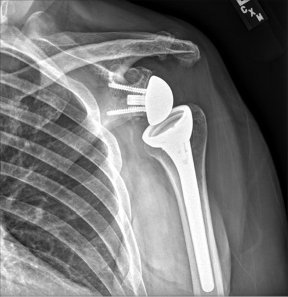

I specialised in all kinds of Knee and Shoulder surgery be it Joint Replacements or Joint Preservation, be it conventional technique Arthroscopic or Robotic

Knee Replacement Surgery, also known as knee arthroplasty, is a surgical procedure that aims to relieve pain and restore function in severely damaged knee joints. It involves replacing the damaged joint surfaces with artificial implants made of metal and plastic.